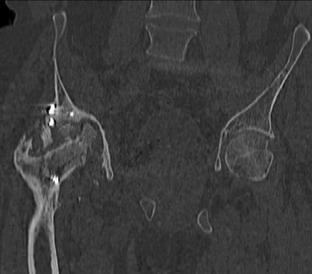

Пациент 49 лет, паровозная травма 23.2.2006, получил вертикальная нестабильное повреждение таза, разрыв левого крестцово-подвздошного сочленения, перелом лонной, седалищной костей слева, T-образный оскольчатый перелом правой вертлужной впадины с переломом заднего края, вывих правого бедра, посттравматическая пояснично-крестцовая плексопатия с обеих сторон, паралич мышц правой голени. В день травмы - вправление вывиха, скелетное вытяжение, 14.3.2006 чрескостный остеосинтез таза. 20.4.2006 остеосинтез правой вертлужной впадины пластинами, осложнившийся нагноением межмышечной гематомы правой ягодичной области. Получал консервативное лечение, было достигнуто полное заживление раны. 24.7.2006 введены илиосакральные винты слева. С декабря 2006 года и по настоящее время ходит на костылях без опоры на правую ногу. Планируется THA. Помогите определиться с вариантом костной пластики? И какую укрепляющую конструкцию использовать?